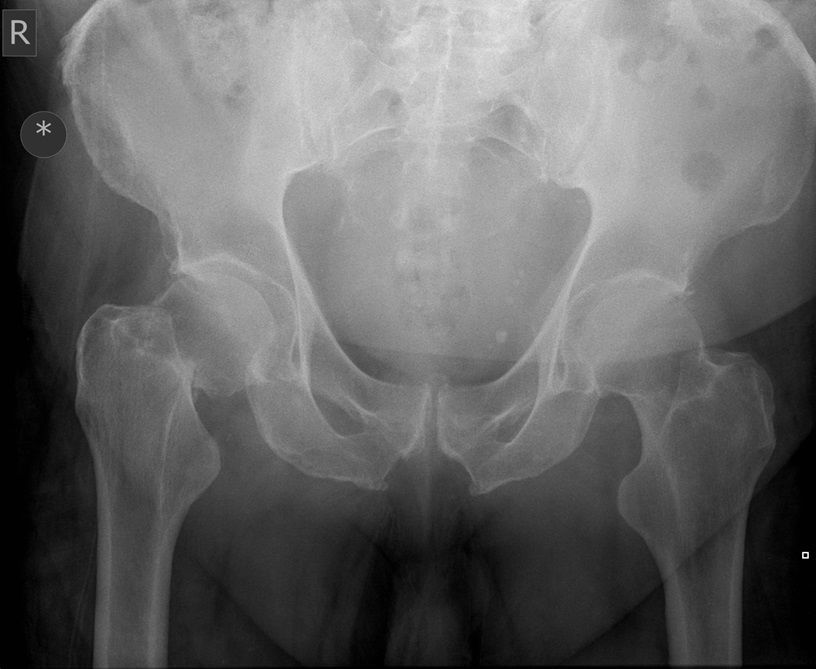

I was hoping you would partake in a study we are doing. We want to establish if there is any bias when deciding an operation based on the radiograph. We understand that the NICE guidelines state that the patient management for hip surgery should not be based on the radiographic findings; rather it should be based on defined criteria. However with that aside what we are requesting is that you look at the film + decide what operation either THR or Hemiarthroplasty. Click the dot + select answer.

Question 3

Question

Which operation would you perform?

Answer

• THR

• Hemiarthroplasty